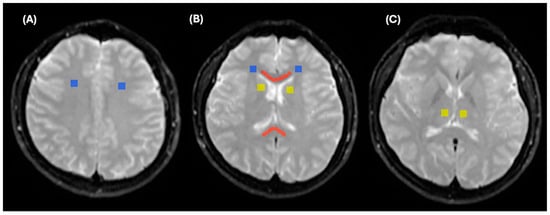

2.2. Lesion Analysis

2.3. MRI Imaging Protocols

2.4. MRI Processing